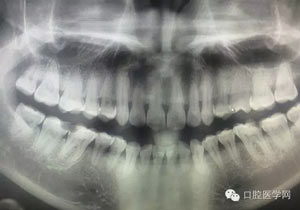

病例2:364647中齲的樹脂充填,現(xiàn)在樹脂的充填材料非常之多,有些時候,我們感覺有了好的材料我們就可以做出好的修復(fù),可是這是在我們有扎實的基本功的基礎(chǔ)上的,我們可以沒有那么好的樹脂,那么多的顏色選擇,修復(fù)的那么的逼真,但是我們至少要恢復(fù)患者牙齒的功能,將腐質(zhì)去除干凈,薄壁弱尖消除掉,選擇好適應(yīng)癥,給患者以盡可能好的修復(fù)。